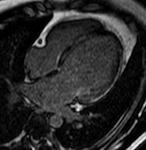

(拡張型心筋症)左室の拡張と中隔に線状の遅延造影像を認めます。